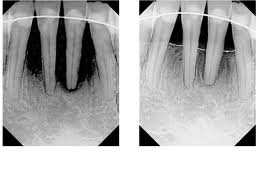

Before and After

Credit: Arizona Center For Laser Periodontal Therapy